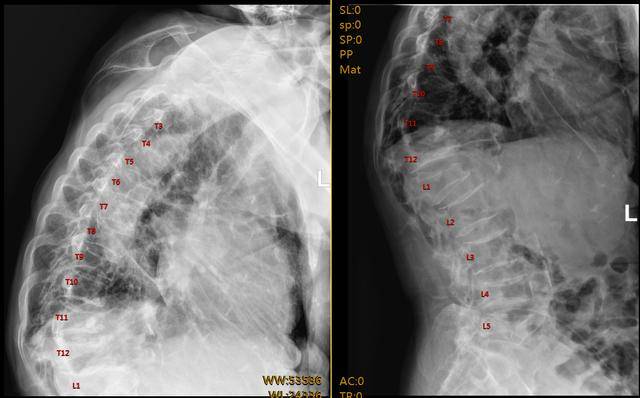

每一个生命,都值得被极致呵护。当老人入院的那一刻,医院立即启动绿色通道,全院聚力开启“生命时速”。从急诊、影像、麻醉、骨科、重症等多学科团队无缝衔接,到初步诊断、影像检查、术前评估、方案制定,所有环节一气呵成,仅用6小时便完成了从入院到手术的全流程,用高效与速度和“病魔”抢时间,用专业与敬业为患者垒起生命的“护盾”,用人文关怀点亮了“医者仁心”的价值坐标。